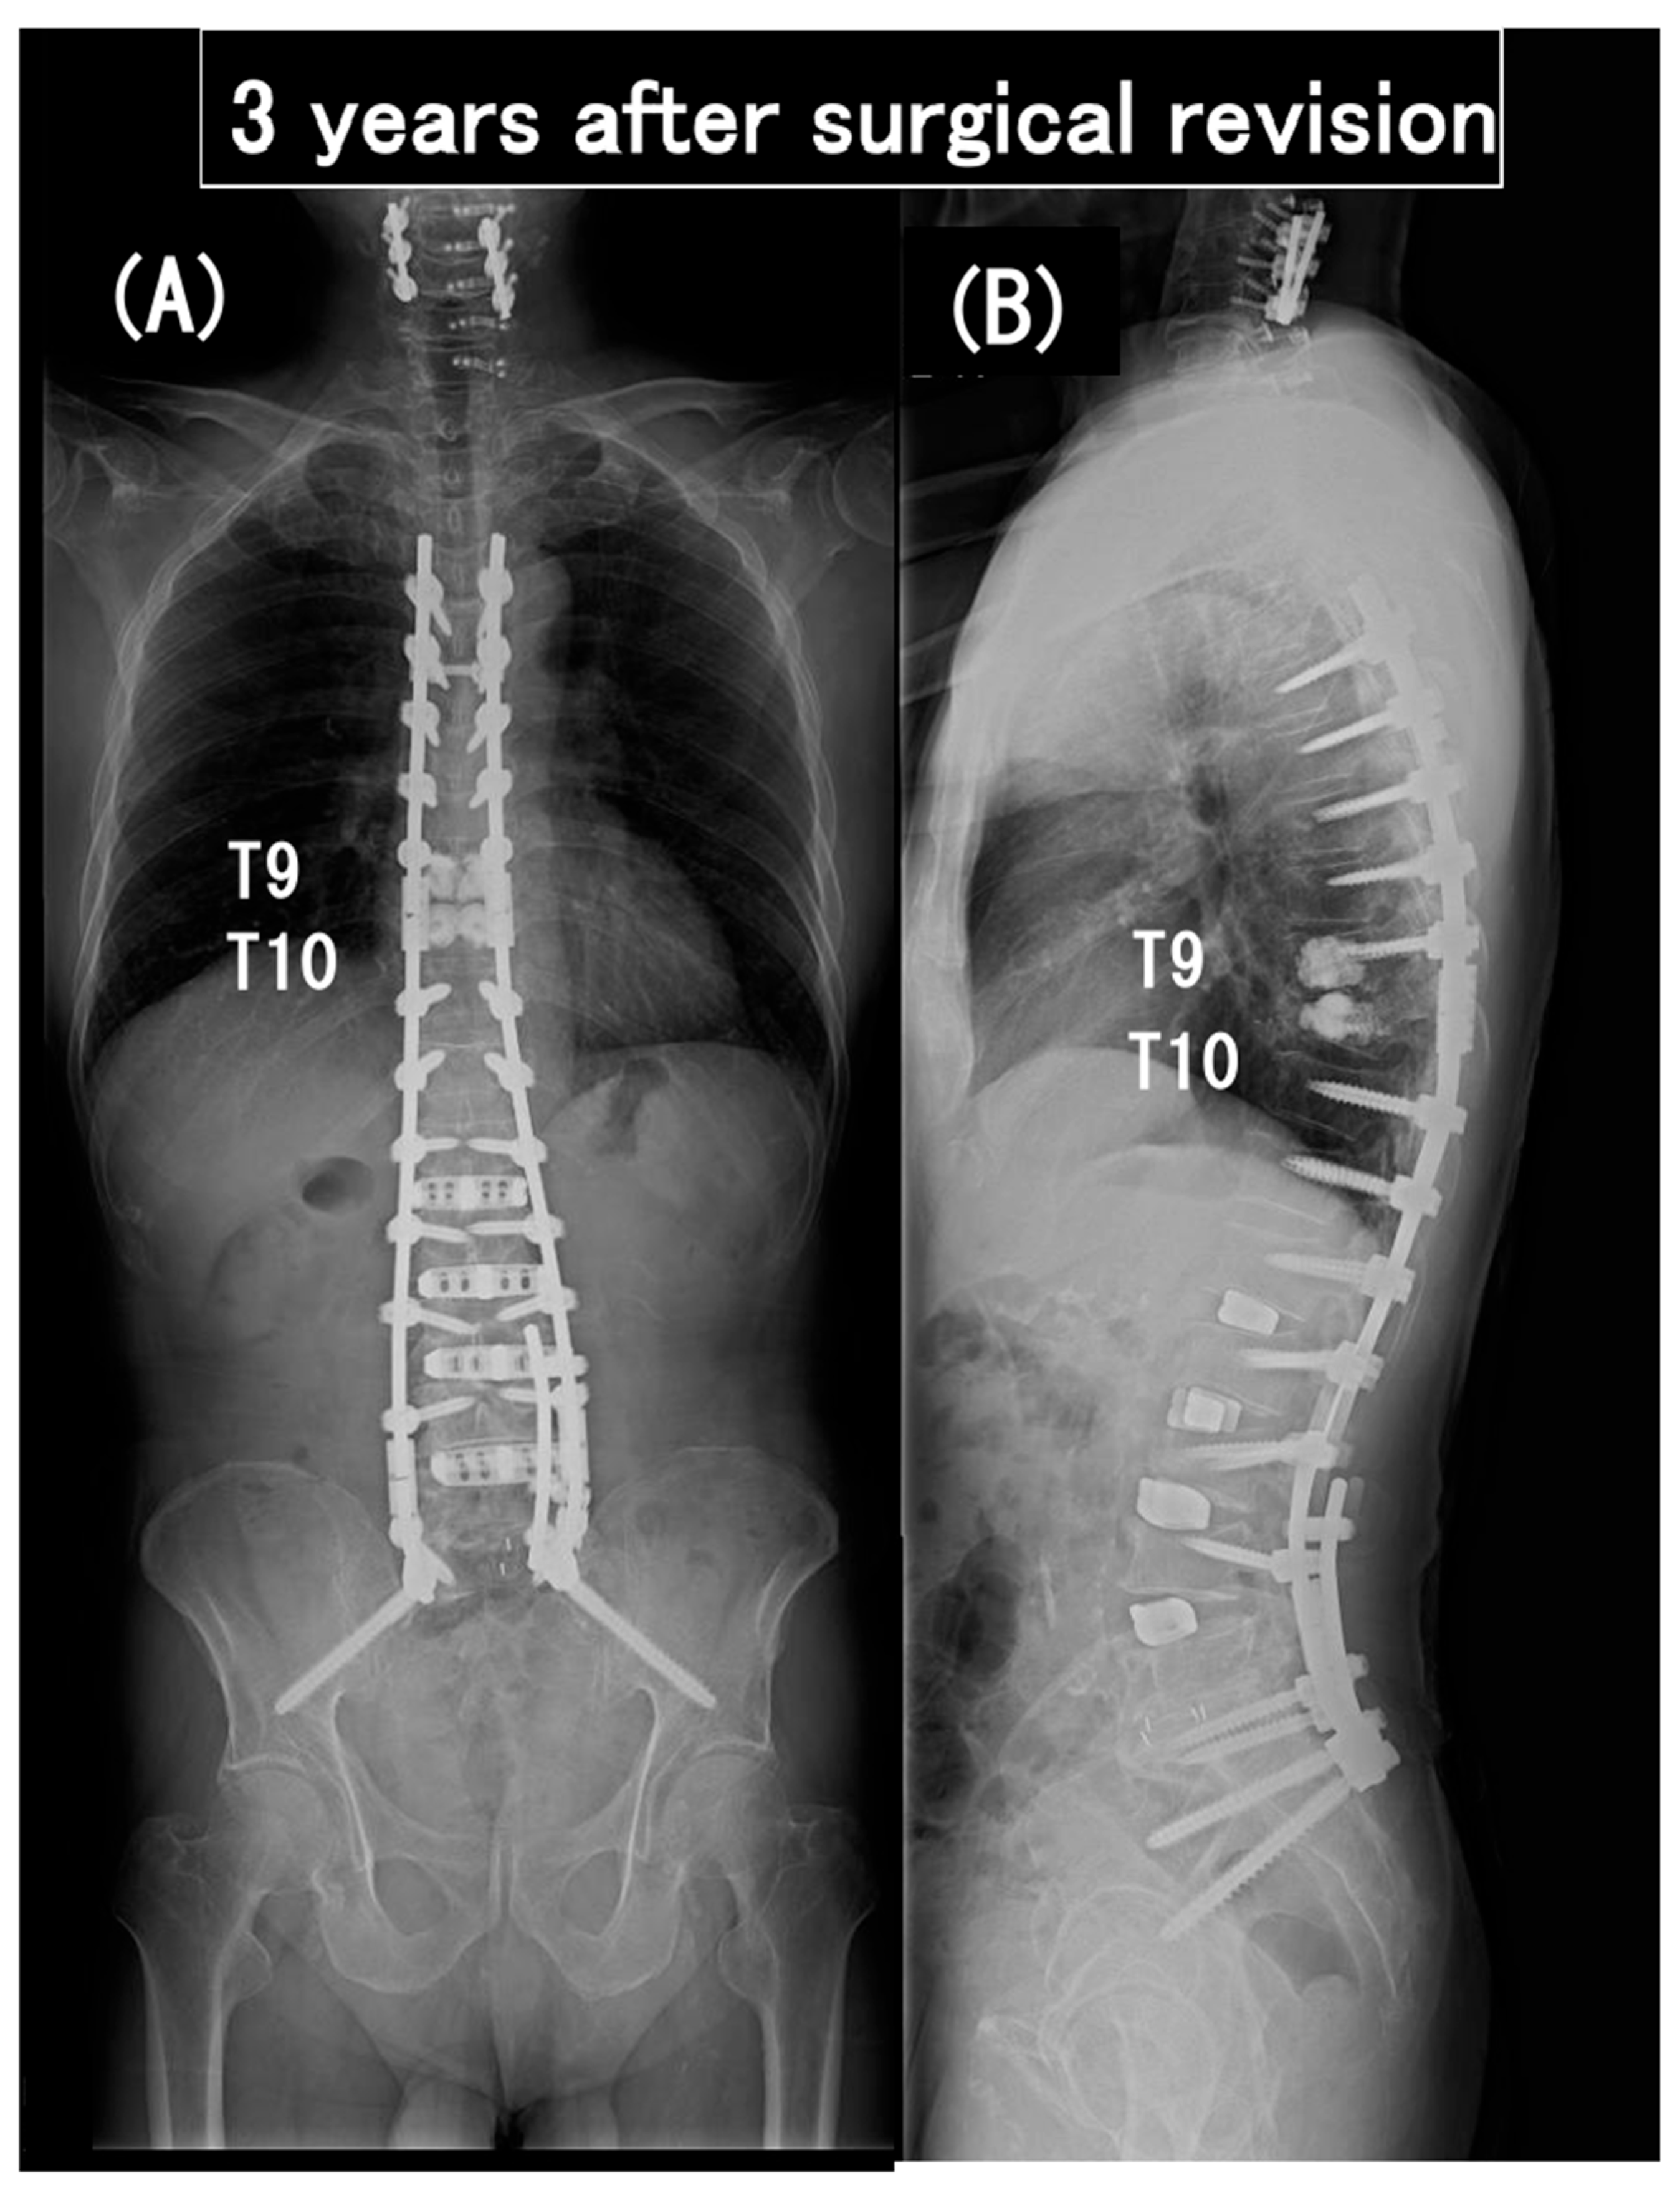

3.6. Case Presentation

- Case no. 6

- Case no. 4